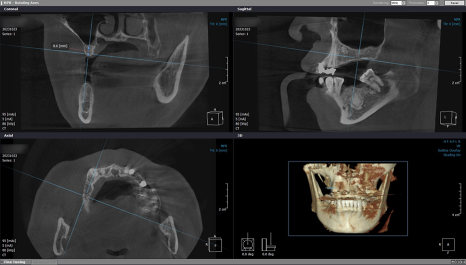

3개월 후 좌측 픽스처 고정력을

ISQ 장비로 확인한 다음

힐링 지대주를 제거하고

코핑을 연결해서 인상과 교합 채득 후

임시 치아로 수복해 드렸습니다.

이어서 우측 임플란트를 위해

재검사를 시행했습니다.

처음과 같이 큰 변화는 없었지만

오차 없이 인공 치근을 식립하려면 검사는 필수죠 ^^